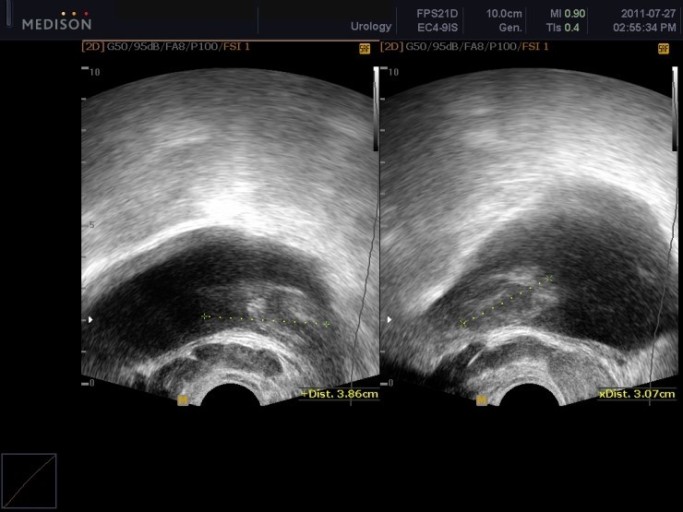

- 정기적인 검진: 특히 50세 이상 남성은 정기적인 전립선 검진을 통해 미리 질환을 예방해야 합니다.